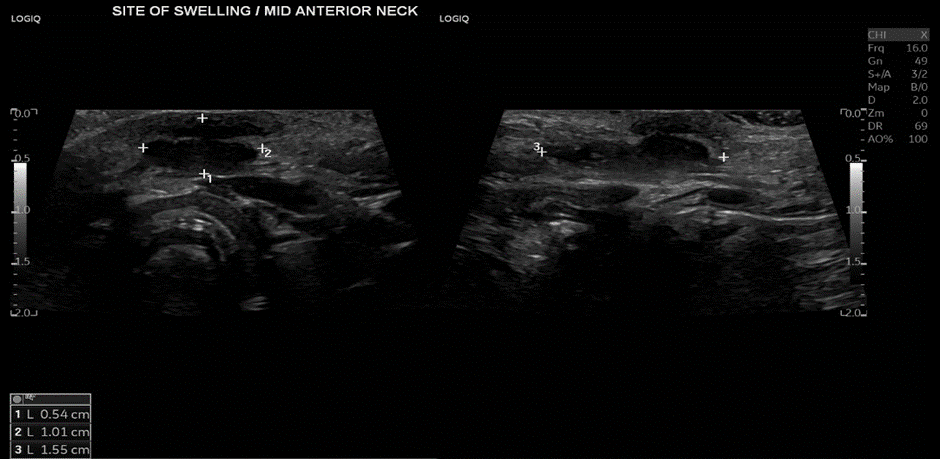

Revaluation of the case one week later in our clinic showed that inflammation subsided, no redness or hotness, no cervical lymph nodes were detected, an ultrasound neck was done and revealed a bilobed hypoechoic lesion located anterior to the hyoid bone, measuring 0.5 x 1 x 1.55 cm, consistent with a thyroglossal cyst, (figure 1).

Figure 1: US neck showing the bilobed swelling